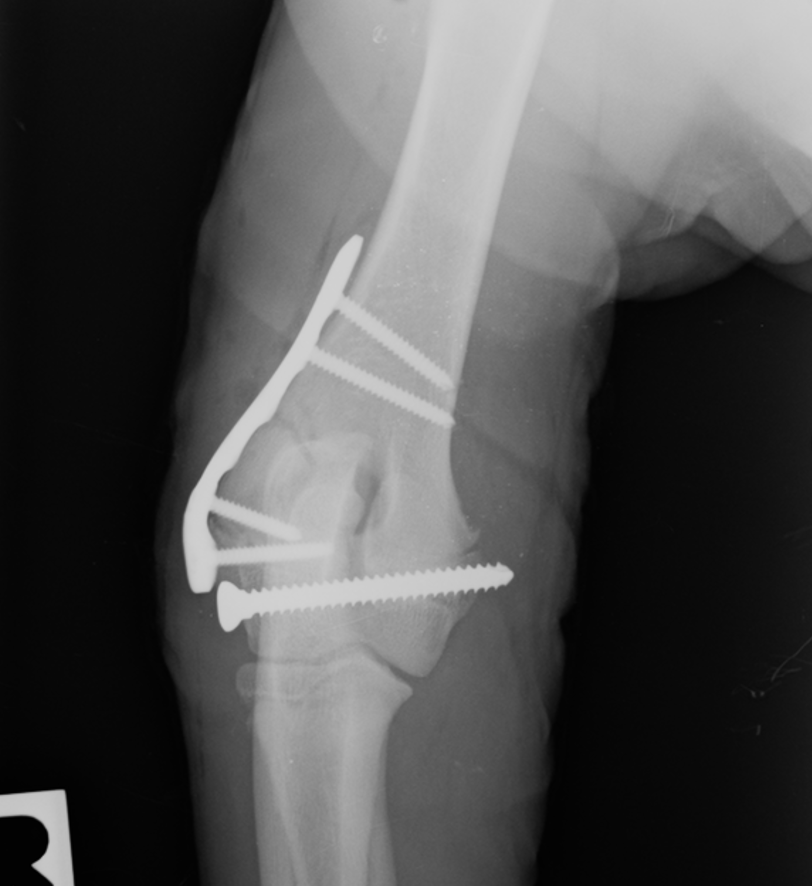

Getting to Grips with the Elbow